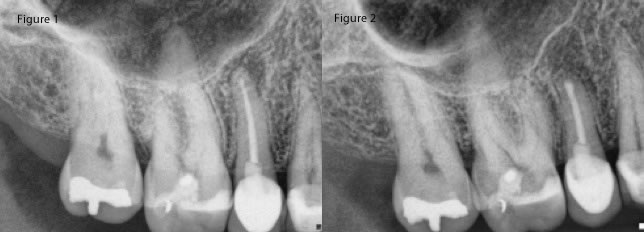

I will say though that while we consider ourselves to be overly safe in our selection process with regards to anatomy, I think that you might be surprised that the treatment is much safer than your original preconceptions. What I mean is that a nearby sinus is not at all an absolute contraindication (figures 1,2,3,4). Additionally, what you might think is too close for a mandibular canal is sometimes not a problem. (figure 5,6,7)

Fig 3: Pre-op #13 near sinus, Fig 4: Immediate post-op #13 and 10 month recall- fistula has not returned.